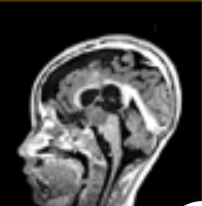

然而不幸的是,21个月后,Anna出现了呼吸道感染,再次检查时发现肿瘤已经侵袭到了肺部,医生做了第3次手术,将左下叶切除,完全拿掉了肿瘤,并进行了淋巴结清扫术。但仅过了4个月,Anna又出现了颅内高压的现象,核磁显示肿瘤早已转移到了脑部,已经有乒乓球那么大,并且足底的病灶也开始再次增长。医生做了第四次手术切除了部分脑肿瘤,但术后Anna的情况非常糟糕,没有自发睁眼,瞳孔不等,肢体痉挛...更糟的是,术后仅3周,肿瘤就长回来了,左脚的隆起也越来越大....这一切的迹象都意味着Anna脆弱的生命进入了倒计时。

2019年2月,Anna开始接受拉罗替尼治疗(口服溶液,100mg/m2)。这款药物的起效时间震惊了所有人,仅14 天出现迅速的临床改善,足底的肿瘤以肉眼可见的速度缩小。3周后,头颅 MRI 显示脑部病灶大幅缩小。在开始使用larotrectinib后5个月,足部病变已完全消退,胸部CT未显示肺部复发迹象!